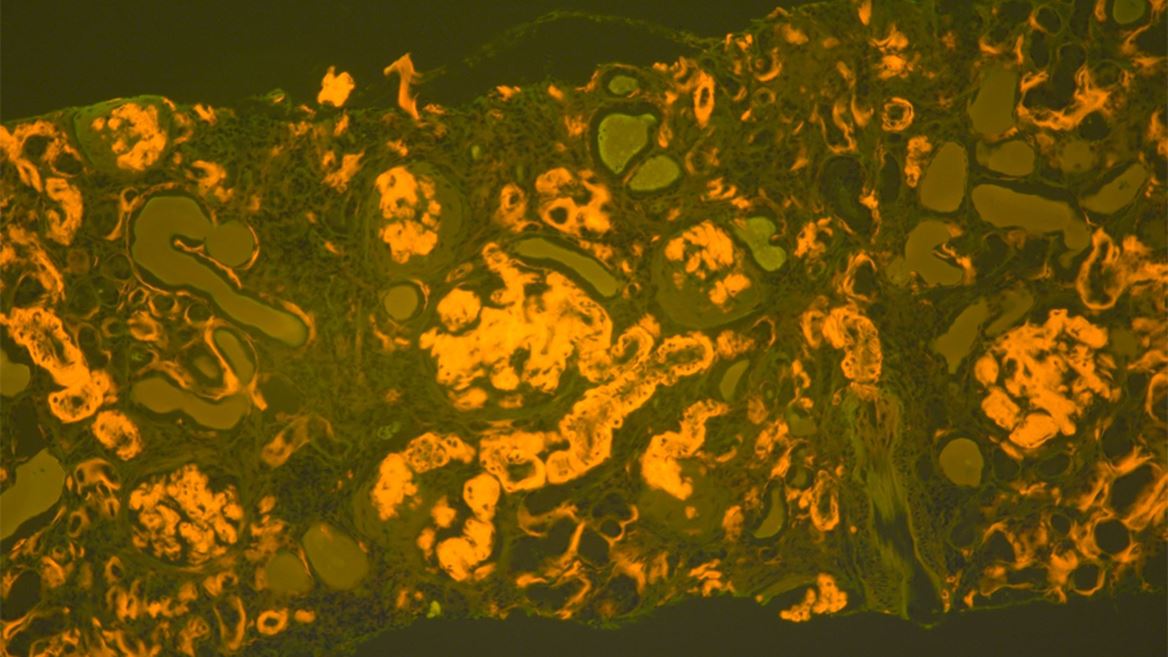

Amyloidosis is a rare but serious disease caused by the buildup of abnormal amyloid deposits in the body. The new guideline aims to support earlier and more accurate diagnosis, which is critical for effective treatment but has often been challenging for laboratories and pathologists.

A multi-disciplinary panel of experts reviewed more than 4,000 studies to develop recommendations on the most accurate methods for detecting amyloid, identifying fibril protein type, and evaluating sample types. The guideline provides pathologists with clear direction on appropriate testing and subtyping of amyloid-positive specimens.

• Congo Red Stain: Remains the standard for amyloid detection; other stains should be validated.

• Fluorescence Microscopy: May improve Congo red sensitivity where available.